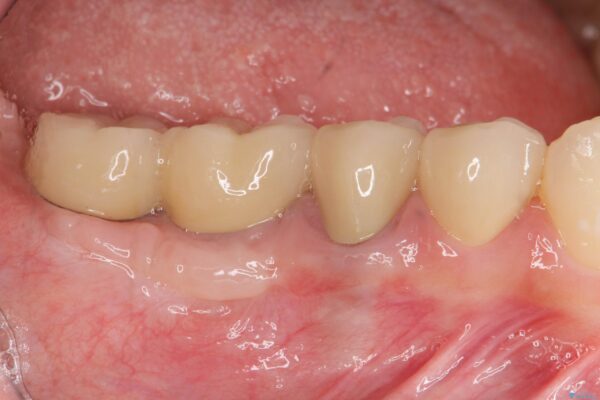

また、機能後のインプラント周囲の清掃性を高めるため遊離歯肉移植術を行っています。

インプラント周囲に強固な歯ぐきを移植することで、歯ブラシがしやすくなりインプラント周囲炎対策となります。

治療後

遊離歯肉移植術を伴うインプラント治療 治療後画像 遊離歯肉移植術を伴うインプラント治療 治療後画像 遊離歯肉移植術を伴うインプラント治療 治療後画像 遊離歯肉移植術を伴うインプラント治療 治療後画像